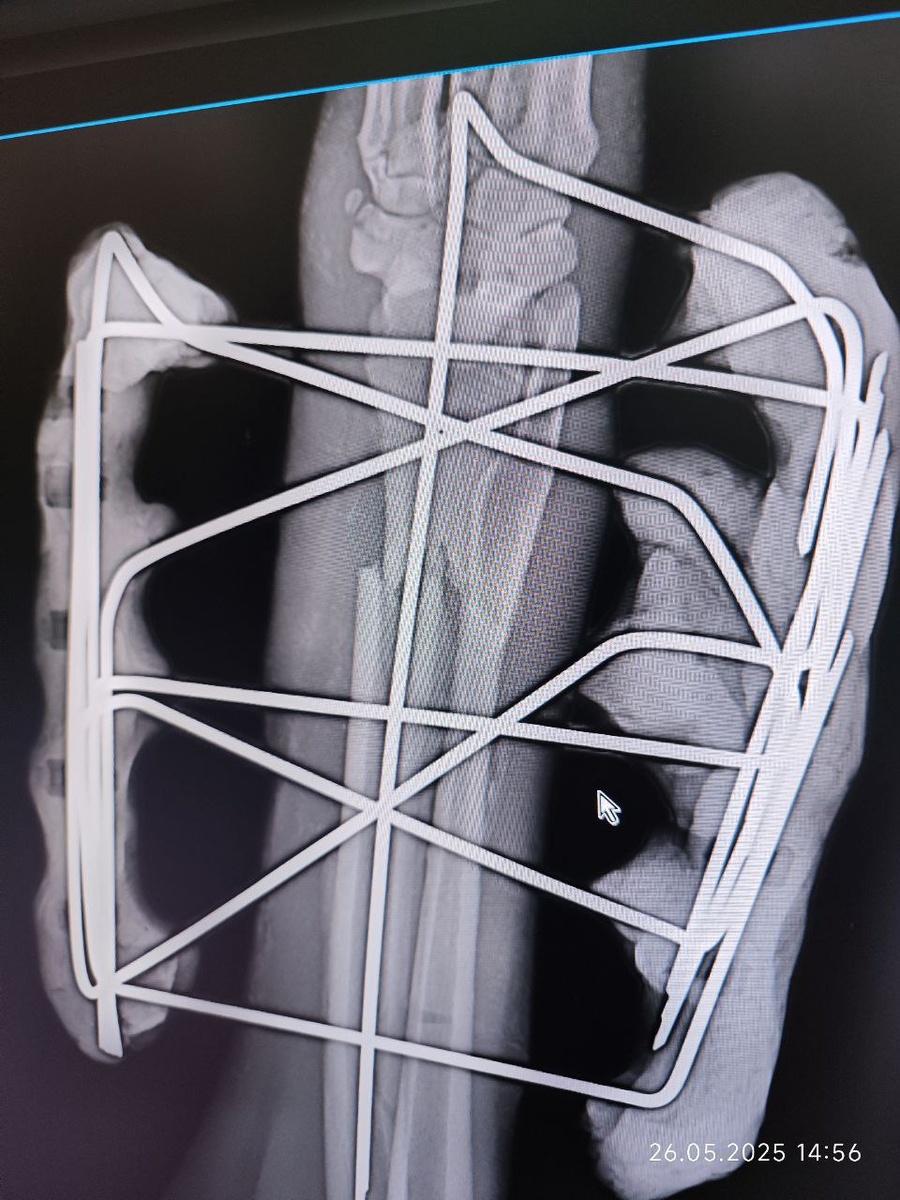

У Норда всё хорошо

У Норда всё хорошо 🥰 #шансожители

У Норда всё хорошо 🥰